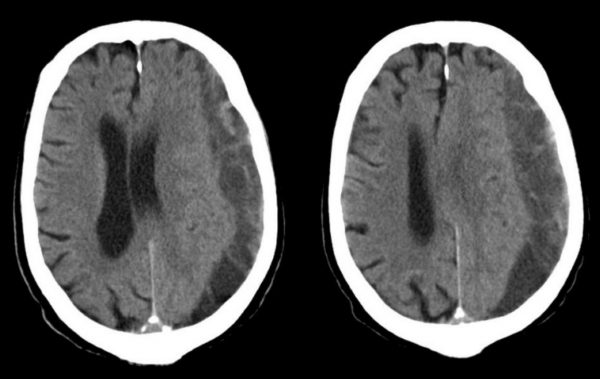

Υποσκληρίδιο Αιμάτωμα: Ποια τα αίτια;

Στις περισσότερες περιπτώσεις η αιτία του υποσκληριδίου αιματώματος είναι κάποιο τραύμα. Για να δημιουργηθεί υποσκληρίδιο αιμάτωμα σε νεαρά άτομα απαιτείται κάποιο σημαντικό τραύμα (όπως πχ. μετά από τροχαίο ατύχημα). Στους ηλικιωμένους όμως παρατηρούνται συχνά υποσκληρίδια αιματώματα ακόμα και μετά από ασήμαντο τραυματισμό.

Αυτό που συμβαίνει κατά τη διάρκεια ενός τραύματος είναι η απότομη «μετακίνηση» του εγκεφάλου εντός του κρανίου, με αποτέλεσμα τη ρήξη των επιφανειακών εγκεφαλικών αγγείων (συνήθως φλεβών). Η ρήξη του αγγείου οδηγεί σε αιμορραγία στο χώρο από όπου περνάνε τα αγγεία, που είναι ο χώρος ανάμεσα στην αραχνοειδή και τη σκληρά μήνιγγα (υποσκληρίδιος χώρος). Παρόλο που το υπαίτιο αγγείο είναι συνήθως κάποια φλέβα, τα υποσκληρίδια αιματώματα που προκαλούνται από ρήξη αρτηρίας δεν είναι τελείως ασυνήθη. Μάλιστα, υπολογίζεται ότι για το 20-30% των υποσκληριδίων αιματωμάτων ευθύνεται η ρήξη κάποιας μικρής αρτηρίας (διαμέτρου <1 χιλ).